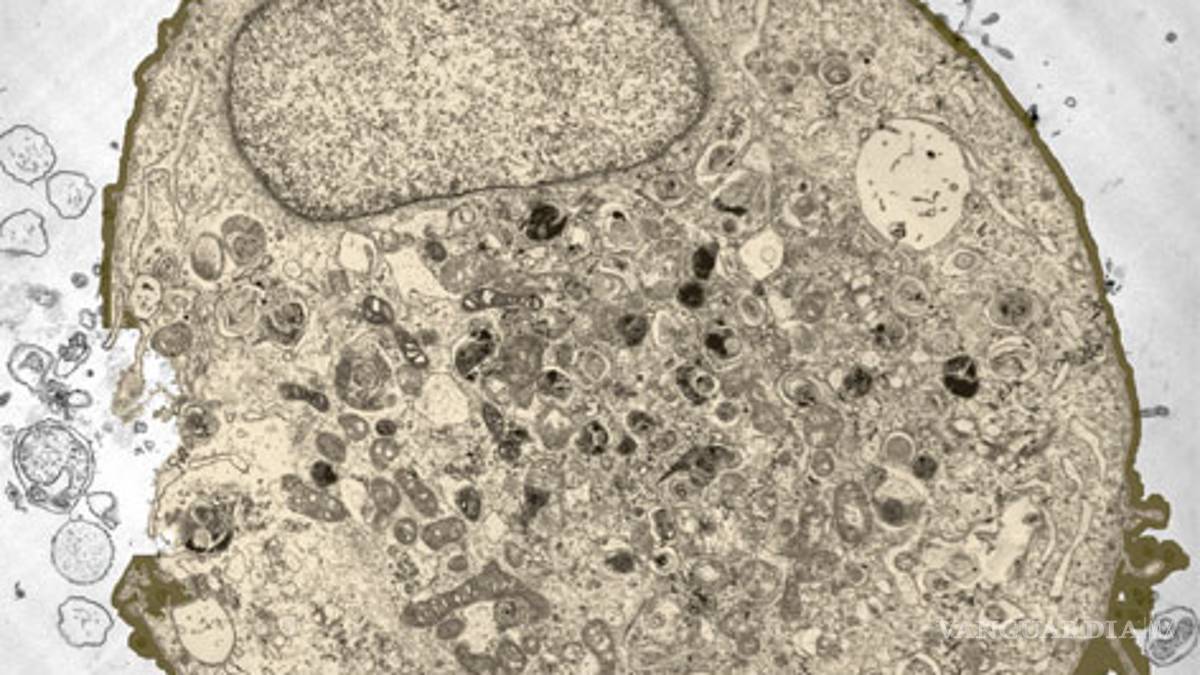

El Fondo Mundial para la Investigación del Cáncer alertó de que en los próximos años la incidencia podría aumentar de forma drástica; los casos de cáncer que se detectan cada año son ya cuatro veces más que el VIH

LONDRES, Ing. El número de casos de cáncer subió un 20 por ciento en el mundo en la última década hasta alcanzar 12 millones de nuevas detecciones al año, según divulgó hoy el Fondo Mundial para la Investigación del Cáncer (WCRF, en sus siglas en inglés) .

La organización alertó que en los próximos años la incidencia de la enfermedad podría aumentar de forma "drástica" y recalcó que los casos de cáncer que se detectan cada año son ya cuatro veces más que las infecciones por VIH (2.6 millones) y muchos se pueden prevenir.

El WCRF, que agrupa a organizaciones sin ánimo de lucro dedicadas a la investigación y la prevención del cáncer, subrayó que 2.8 millones de los casos que se detectan al año están ligados a la dieta, la actividad física y el sobrepeso.